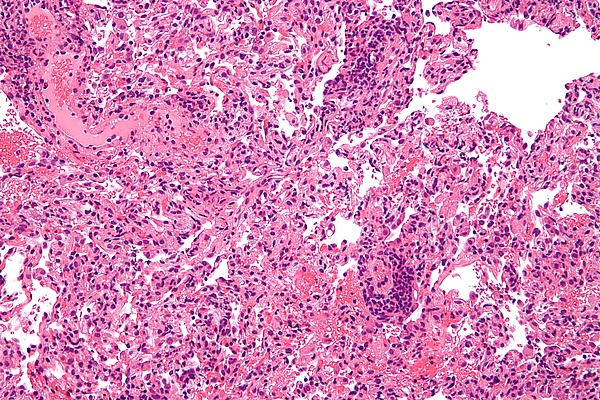

Реа́кция отторже́ния транспланта́та — иммунный ответ реципиента на пересадку чужеродного органа или ткани (аллотрансплантацию). Относится к реакциям трансплантационного иммунитета. Различают молниеносное (развивается через минуты после подключения органа к кровотоку), острое (0-3 недели после операции) и хроническое отторжение (через несколько месяцев или позже).